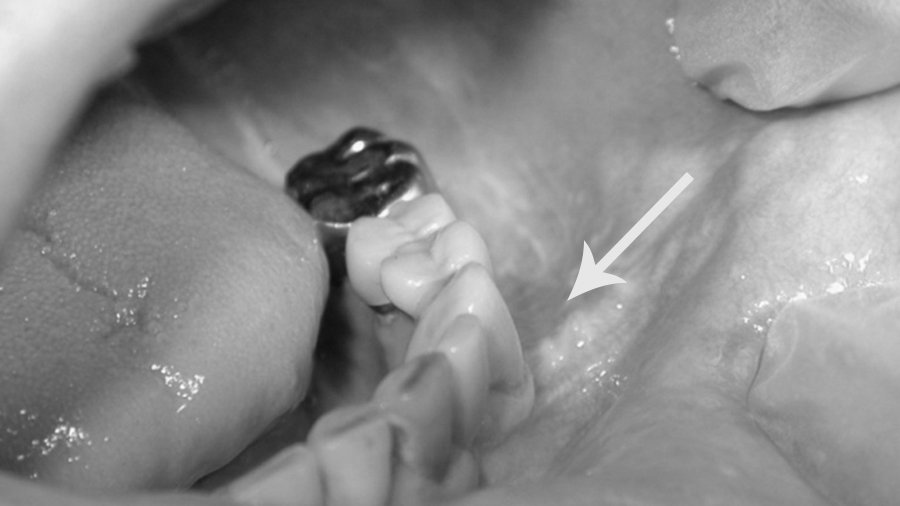

Alergia a próteses dentárias com metal em mulheres : área com inflamação gengival associada à próteses dentárias

A primeira suspeita para qualquer problema inflamatório nas gengivas é a gengivite associada à placa bacteriana. Em algumas pacientes essas inflamações podem evoluir para áreas já com a presença de algum tipo de retração gengival, além dos sinais inflamatórios característicos da alergia a próteses dentárias.

Após algumas consultas sem progresso do tratamento, a hipótese de alergia a próteses dentárias como causa para inflamações ou retrações da gengiva deve ser considerada e os tratamentos para a solução do problema devem ser imediatamente iniciados.

Inflamação e início de retração gengival em paciente alérgico a metal de próteses dentárias convencionais